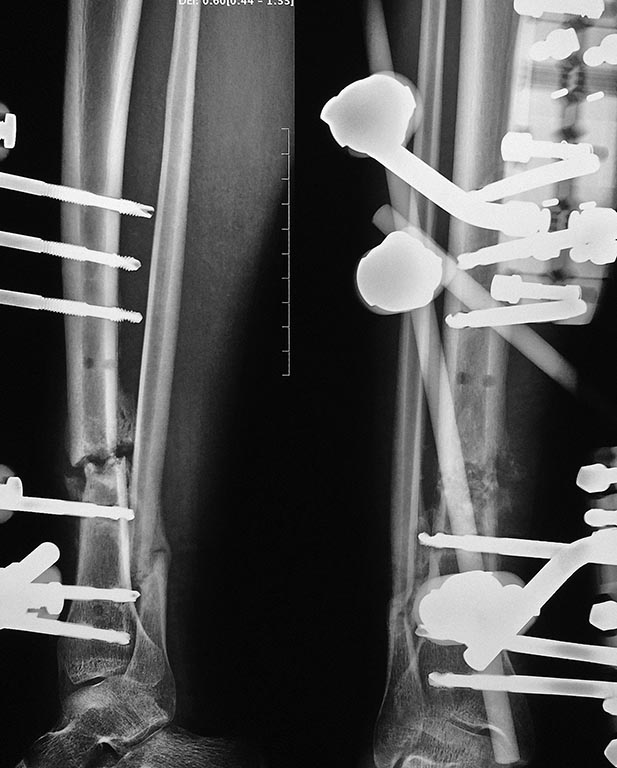

Больной 18 лет, 5 месяцев назад сбит автомашиной, проходил лечение в

нашем отделении с диагнозом "Автотравма, ЗЧМТ среднетяжелая, ушиб

головного мозга, открытый перелом нижней челюсти, закрытый перелом

правой бедренной кости, открытый перелом костей правой голени".

5 месяцев назад выполнены открытые репозиции отломков бедренной кости и

нижней челюсти, остеосинтез. На голени была ранка в проекции перелома

5х5 мм., наложен стержневой аппарат.

Ранка зажила через 2 недели после травмы без признаков воспаления.

Переломы бедренной кости и челюсти консолидировались, но контрольных

рентгенограммах костей голени нет сращения большеберцовой кости. Местно

- признаков воспаления нет. Ходит на костылях, приступая на больную

ногу. Посоветуйте, пожалуйста, тактику дальнейшего лечения. Заранее

благодарны за любые предложения!